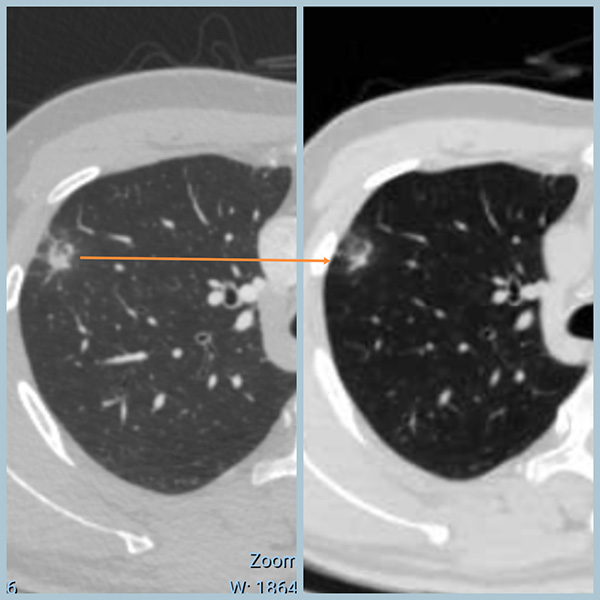

两次CT对比,变化(缩小吸收)一目了然!

3、CT上病变再典型,恶性特征再多,也有看走眼的时候。良恶性病变CT表现并不是泾渭分明,它们是有交叉的。

4、对于年轻的患者,首次发现肺结节,可以给自己一个消炎的机会,也许自己就是幸运之子。